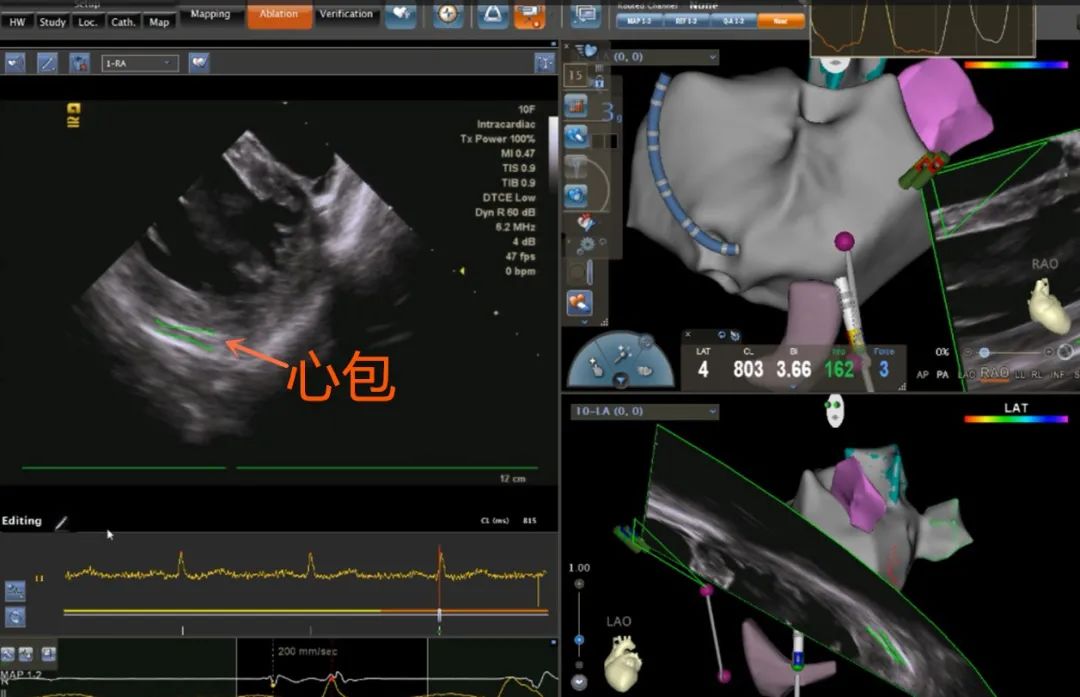

术中,穿刺股静脉,首先由股静脉置入腔内超声导管置右心房,不同操作旋转导管,建立冠状窦、左心房体部、左右侧上下肺静脉、左心耳、食道等重要解剖结构。随后,穿刺锁骨下静脉,置入冠状窦电极,经股静脉置入导引导丝,沿导丝送入穿刺鞘、穿刺针,进行房间隔穿刺。通过超声检测心包下,进行射频消融术隔离肺静脉,完成肺静脉隔离,证实房颤起源于肺静脉,消融隔离后患者房颤反复诱发不再发作,手术成功。术后患者恢复良好,观察两天康复出院。

超声检测心包下,进行射频消融术隔离肺静脉